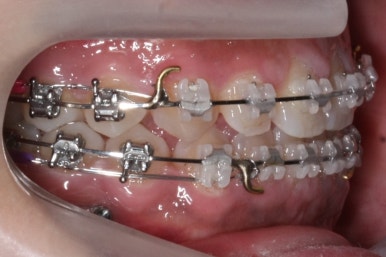

위 사진은 부산치아교정치과에 내원하셨을 대 당시의 입안 모습입니다.

치아들 사이에 전반적으로 틈이 많이 있는 상태입니다.

장치 부착 모습입니다.

이번에 부산치아교정치과에서 사용한 장치는 클리피씨라는 자가결찰 세라믹입니다.